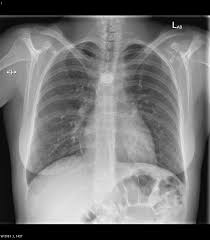

Which plane was the following x-ray taken?

Frontal or coronal